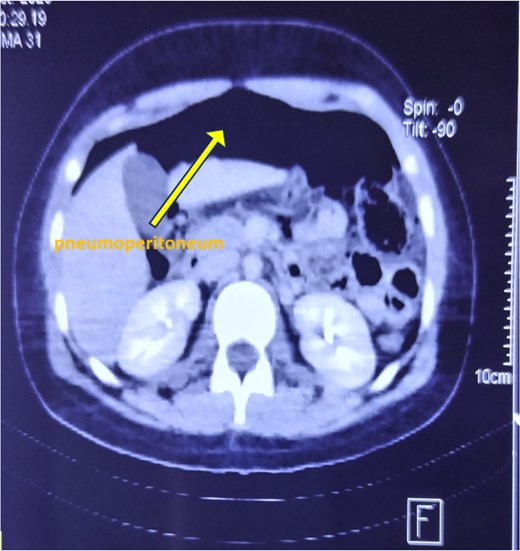

An upright abdominal X-ray revealed massive bilateral pneumoperitoneum (Fig. 2), contrasting with the subtle abdominal signs. This clinical-radiological mismatch prompted an abdominopelvic CT scan, which confirmed the presence of abundant free intraperitoneal air, without clearly identifying the perforation site (Fig. 3).

Axial CT scan of the abdomen showing extensive pneumoperitoneum.